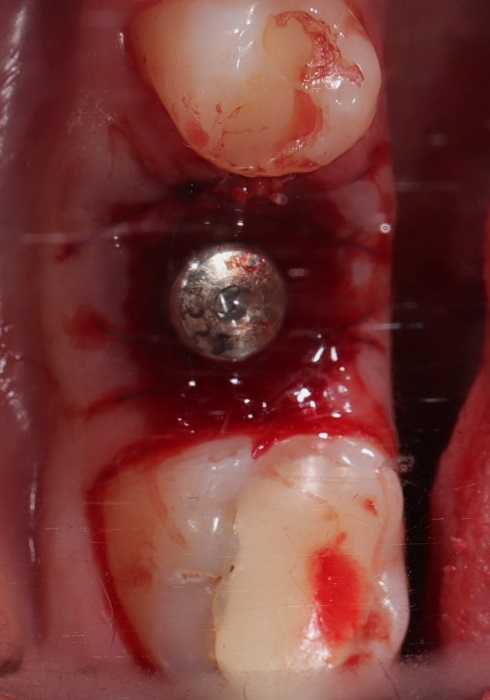

Зуб 46 разрушен очень сильно, и больше не может выполнять функции.

На фото вид операционной зоны после операции и через 3 месяца дней после.

Как и всегда, я стараюсь провести максимальный комплекс в одну операцию: удаление, имплантация, костная пластика, пластика слизистой, установка заживляющего абатмента.

P/S Такие одномоментные операции упрощают и ускоряют работу, сохраняя объём костной ткани и слизистой. В результате мы получаем отличные условия для протезирования и результат нашей работы становится максимально прогнозируемым.

Протезировать, а тем более реставрировать его бесполезно и бессмысленно. Принято решение заменить его имплантом Strauman SLActive (система входит в топ 5 по миру).

Я провёл много операций разной степени сложности. Много людей доверились мне. Но все же еще более высшая степень признания — когда тебе доверяют доктора! Доверяют настолько, что становятся именно твоими пациентами!

46 — трещина в медиальном корне — причина титанов штифт установленный под неправильным углом. Как следствие трещины переодические ноющие боли после приема пищи.

Две недели после операции.

Что сделали: атравматичное удаление, установка импланта Straumann BLT 4.1x10mm, формирователь, костная пластика, пластика слизистой, APRF. Операцию провели одномоментно — сохранили объём кости, слизистой.